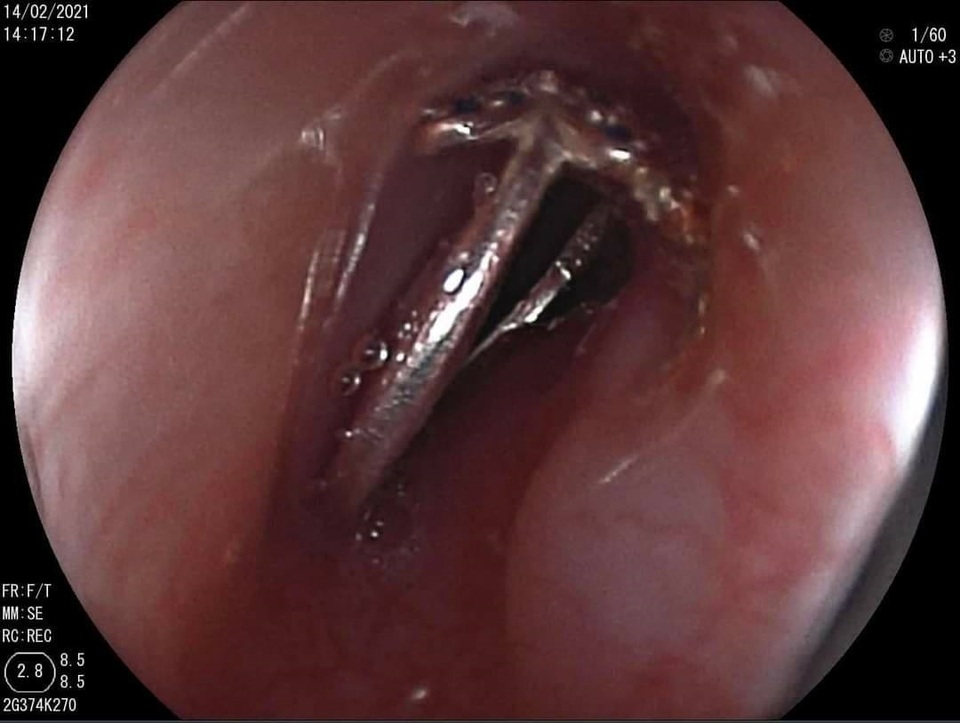

Chiếc nhẫn nằm chắn ngay vị trí 1/3 trên thực quản khiến bé bị nghẹn và khóc nấc liên tục

Bác sĩ Lê Đức Lộc, khoa Tiêu hóa đã phối hợp cùng ê kíp gây mê đang trực Tết khẩn trương can thiệp cho bệnh nhi. Trên hình ảnh camera nội soi, bác sĩ phát hiện, dị vật là chiếc nhẫn nằm chắn ngay vị trí 1/3 trên thực quản. Chiếc nhẫn mắc kẹt ghim chặt niêm mạc khiến bé bị nghẹn và khóc nấc liên tục.

Các bác sĩ đã thận trọng kiểm tra các mô mềm xung quanh đề phòng nguy cơ bệnh nhi bị chiếc nhẫn có nhiều họa tiết sắc nhọn đâm xuyên qua thực quản. Sau khi xác định vị trí chiếc nhẫn bị kẹt chưa gây ra những tổn thương nghiêm trọng, bác sĩ đã nhẹ nhàng kéo dị vật ra ngoài giúp bệnh nhi thoát khỏi nguy cơ bị dị vật lọt vào đường tiêu hóa gây thủng hoặc tắc ruột.